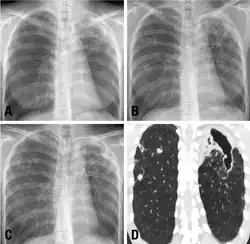

Mycobacterium celatum has been shown to cause fatal disease in both immunocompetent and immunocompromised patients. Clinical symptoms include cough, malaise, and weight loss associated with cavitary lesions and pulmonary infiltrates, whereas the initial laboratory testing includes positive acid-fast stain.